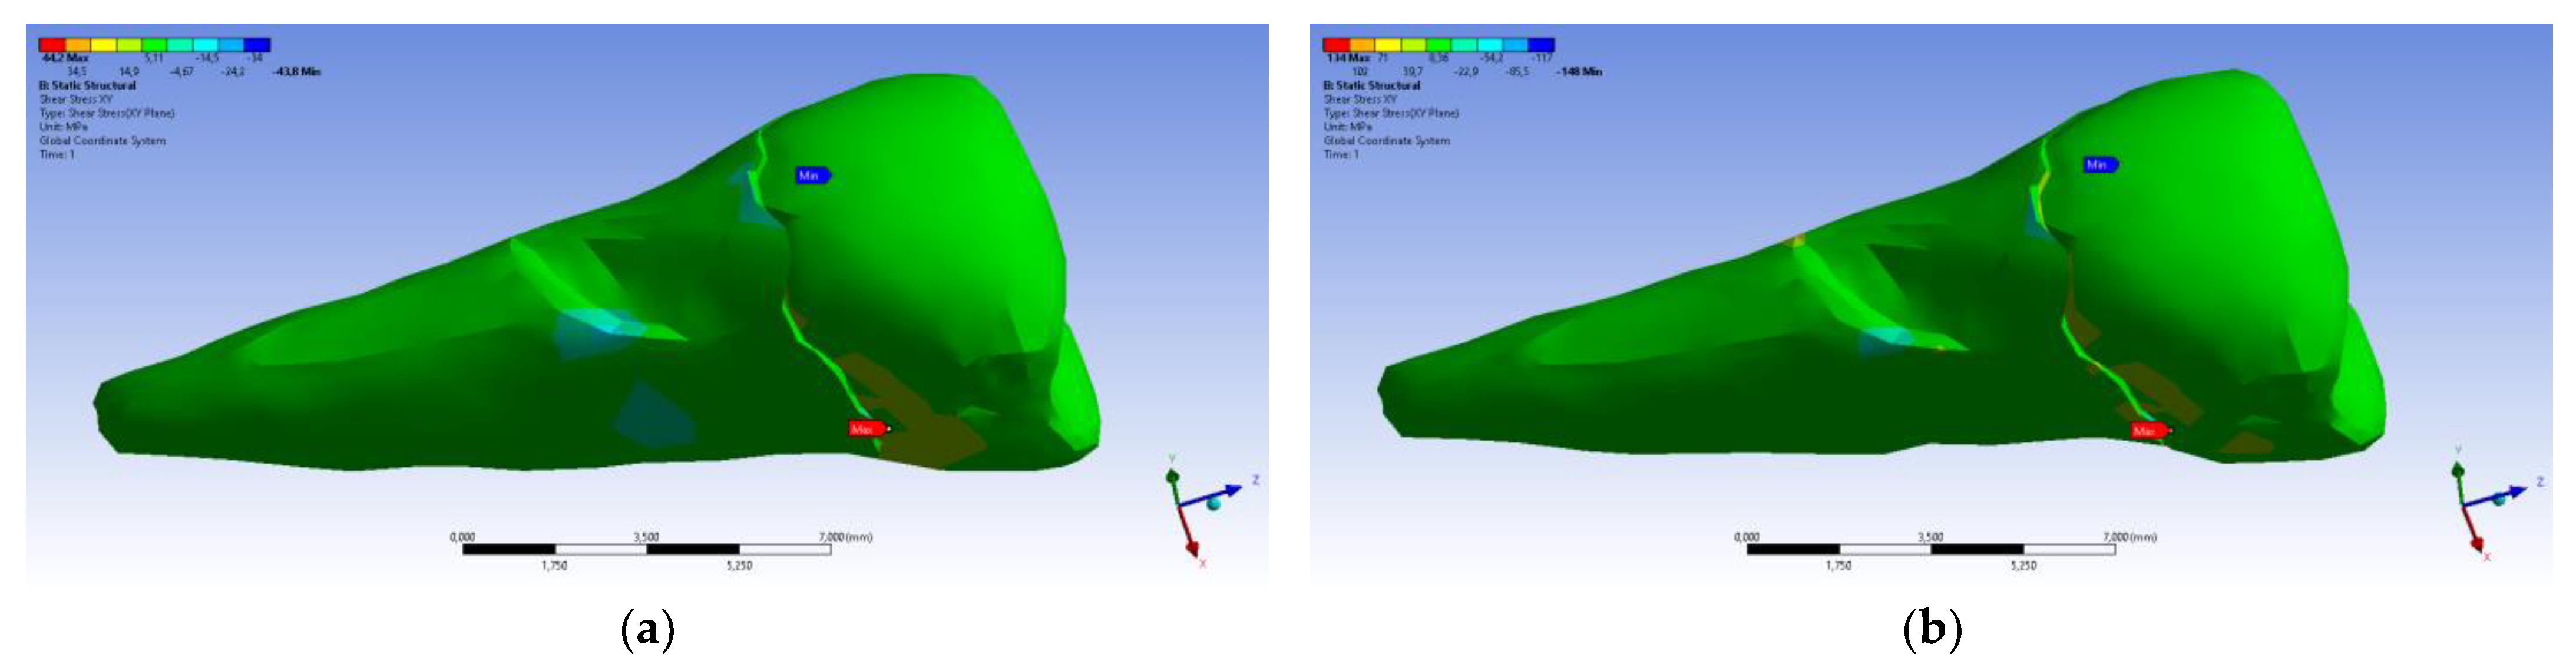

3. Finite Element Analysis (FEA) of Mandibular Right Premolars

| Total Deformation | Deformation in X Direction | Deformation in Y Direction | Deformation in Z Direction | Equivalent Stress | Normal Stress X | Normal Stress Y | Normal Stress Z | Maximum Main Stress | Minimum Main Stress | Tangential Stress XY | Tangential Stress YZ | Tangential Stress XZ | |

|---|---|---|---|---|---|---|---|---|---|---|---|---|---|

| Minimum | 0 mm | −4.24 × 10−3 mm | −2.52 × 10−2 mm | −1.56 × 10−2 mm | 1.01 × 10−6 MPa | −35.6 MPa | −57.1 MPa | −104 MPa | −15.2 MPa | −152 MPa | −43.7 MPa | −39.6 MPa | −56.3 MPa |

| Maximum | 2.77 × 10−2 mm | 3.57 × 10−3 mm | 6.98 × 10−4 mm | 4.78 × 10−3 mm | 248 MPa | 61.5 MPa | 177 MPa | 72.2 MPa | 195 MPa | 21.4 MPa | 44.2 MPa | 117 MPa | 22.2 MPa |

| Minim. in | Cementum | Cementum | Enamel | Enamel | Cementum | Cementum | Enamel | Enamel | Enamel | Cementum | Enamel | Enamel | Cementum |

| Maxim. in | Enamel | Enamel | Cementum | Enamel | Cementum | Enamel | Enamel | Enamel | Enamel | Enamel | Cementum | Cementum | Cementum |

| Total Deformation | Deformation in X Direction | Deformation in Y Direction | Deformation in Z Direction | Equivalent Stress | Normal Stress X | Normal Stress Y | Normal Stress Z | Maximum Main Stress | Minimum Main Stress | Tangential Stress XY | Tangential Stress YZ | Tangential Stress XZ | |

|---|---|---|---|---|---|---|---|---|---|---|---|---|---|

| Minimum | 0 mm | −6.1 × 10−3 mm | −9.02 × 10−2 mm | −3.99 × 10−2 mm | 1.02 × 10−6 MPa | −112 MPa | −199 MPa | −278 MPa | −65.5 MPa | −470 MPa | −148 MPa | −176 MPa | −178 MPa |

| Maximum | 9.28 × 10−2 mm | 1.83 × 10−2 mm | 1.38 × 10−3 mm | 3.12 × 10−2 mm | 780 MPa | 61.5 MPa | 649 MPa | 304 MPa | 704 MPa | 73.8 MPa | 134 MPa | 370 MPa | 78.6 MPa |

| Minim. in | Cementum | Cementum | Enamel | Enamel | Cementum | Cementum | Enamel | Enamel | Enamel | Cementum | Enamel | Enamel | Cementum |

| Maxim. in | Enamel | Enamel | Cementum | Enamel | Cementum | Enamel | Enamel | Enamel | Enamel | Enamel | Cementum | Cementum | Cementum |